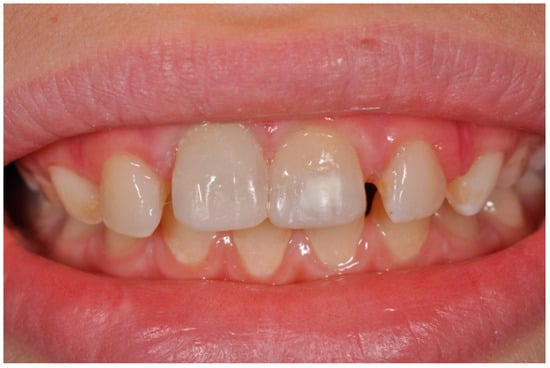

External Root Resorption Management of an Avulsed and Reimplanted Central Incisor: A Case Report

2. Case Report